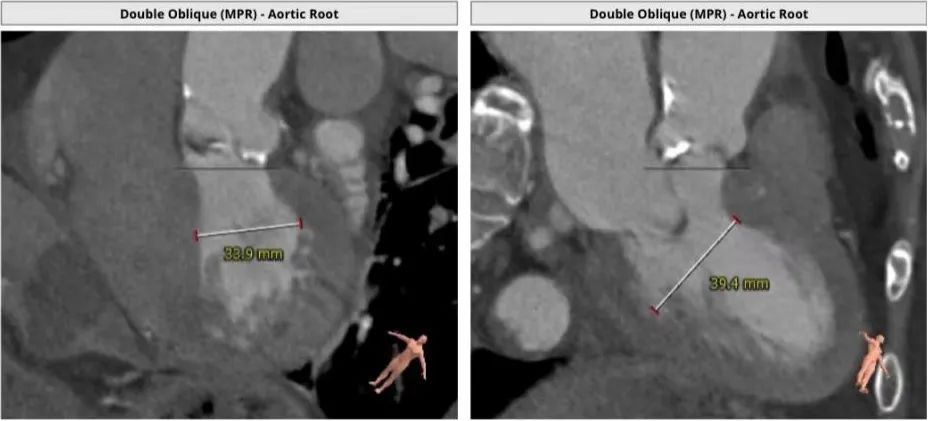

CT

瓣环:20.5mm LVOT:19.2mm

瓣叶分型:三叶瓣 STJ:25.3mm AO:35mm

钙化积分:281mm³

心室大小:33.9mm